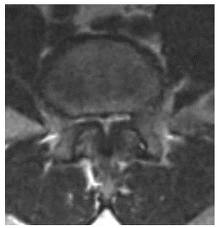

Imagem de Ressonância com Estenose grave do canal lombar.

Note a diferença de uma Ressonância de um canal vertebral normal.